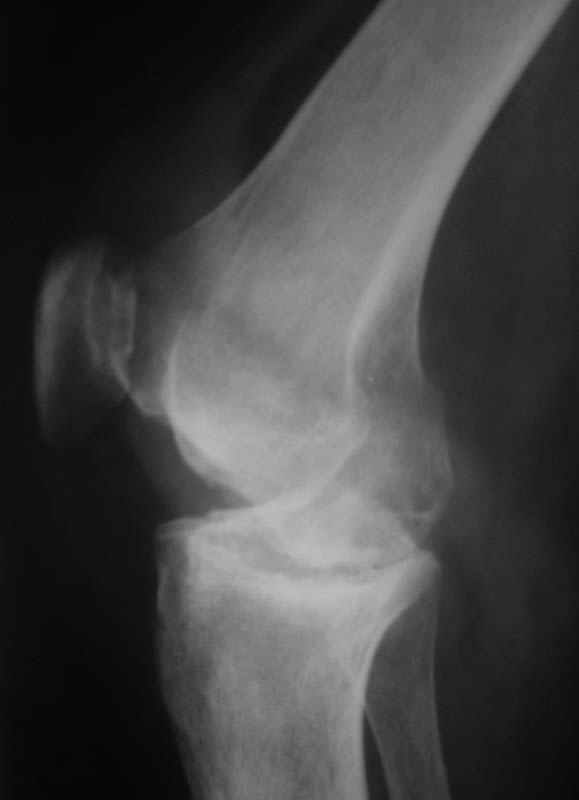

Уважаемые коллеги! Женщина, 28 лет. Страдает ревматоидным полиартритом, гормонозависима. 6 месяцев назад перенесла тотальное эндопротезирование левого тазобедренного сустава по поводу протрузионного коксита.

Использована цементная версия с пластикой дна впадины измельченной аутокостью и гранулами гидроксиапатита. Субъективное улучшение после операции. Улучшилось и стабилизировалось общее состояние. В настоящее время затруднено передвижение из-за поражения правого коленного сустава. Болезненный и <болтающийся> сустав. Предполагается замена сустава протезом без сохранения задней крестообразной связки. Возможные варианты? Заранее благодарю! С уважением,А.В.ВладзимирскийДонецкий НИИ травматологии и ортопедииДонецк, Украина

В случаях ревматоидного артрита с деструктивными изменениями сустава мы стараемся применять конструкции типа RT-Solution (Plus) или AGC (Biomet) из-за высокой вероятности нестабильности также и коллатеральных связок. Эти эндопротезы не требуют сохранения связок вообще. Выбор обусловлен также исходной вальгусной (варусной) деформации.